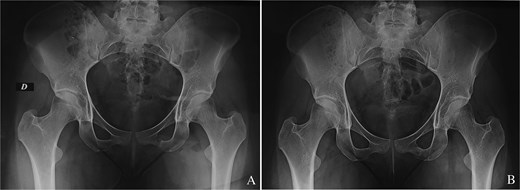

The patient received acetylsalicylic acid, with partial clinical improvement. The decision was made to perform a surgical drilling and curettage of the tumour with the help of a customized 3D-printed guide (Fig. 2A–C). The patient underwent surgery on a standard table, in supine position, under general anaesthesia. A mini-Pfannenstiel approach (on the pubic symphysis) was performed to expose the proximal and medial border of the left iliopubic ramus, which served as a fixed landmark for positioning the guide (Fig. 3A). Once the guide had been pinned in place, a K-wire was inserted in the direction of the tumour. A fluoroscopic check verified the K-wire positioning (Fig. 3B). A soft tissue protection instrument was used to guide the cannulated drill bit towards the tumour (Fig. 3C). Drilling and curettage of the lesion was performed under fluoroscopic control with anteroposterior, inlet, and outlet views of the pelvis (Fig. 3D and E). The anatomopathological examination confirmed the diagnosis of osteoid osteoma, which was completely resected. Pain disappeared in the immediate postoperative period. At 24-month follow-up, we did not note recurrence of the tumour (Fig. 4A and B). Written informed consent was obtained from the patient.

(A) Immediate anteroposterior pelvis X-ray showing the tumour resection. (B) Last follow-up anteroposterior pelvis X-ray showing the absence of tumour recurrence.